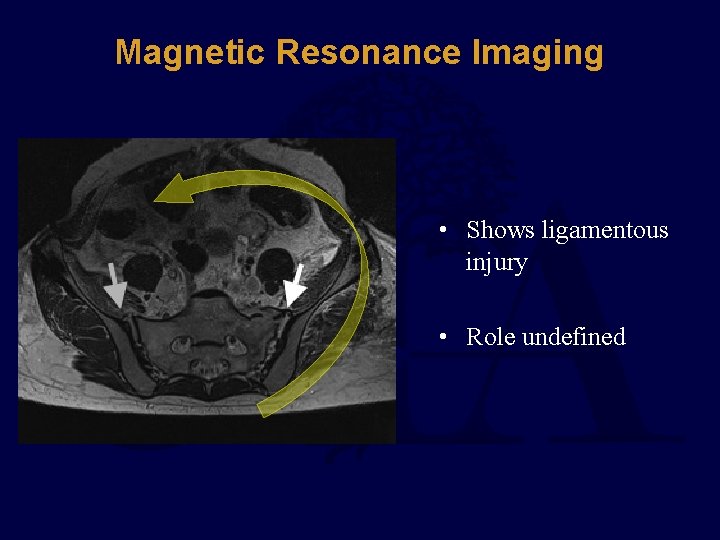

Magnetic Resonance Imaging • Shows ligamentous injury • Role undefined